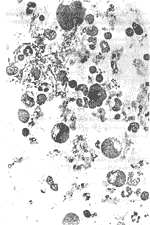

3. เบาหวาน

โรคเบาหวานเป็นที่ควรจะได้รับความสนใจ เพราะเป็นกันแพร่หลาย ทั่วโลก และมีจำนวนเพิ่มขึ้นเรื่อยๆ เป็นโรคครุกเงียบๆ

จึงดูไม่น่ากลัวหากแต่จะบั่นทอนสุขภาพให้ลดถอยลง และมีโรคแทรกซ้อนที่มีอันตรายร้ายแรงเกิดตามมา เช่น ตาบอด หร้อ ต้อกระจก ฝีฝักบัว เท้าเน่าดำอาจจะต้องตัดทิ้ง ประสาทเสื่อม ความรู้สึกทางเพศ

เสื่อมถอยหรือหมดไปในที่สุด และอาจมีโรคติดเชื้อตามมา หรือเป็นโรคไต โรคหัวใจ โรคหลอดเลือดตีบ หรือเส้นเลือดแตกในสมอง ตลอดจนหมดสติ เพราะกรดคั่งในร่างกาย

จากสถิติ พบว่า คนเป็นเบาหวานมีโอกาสตาบอดมากกว่าผู้ไม่เป็นเบาหวานถึง 17 เท่า

มีโอกาสเป็นเท้าเน่าดำ(แกงกรีน) มักถูกตัดขามากกว่าคนปกติ 5 เท่า

มีโอกาสเป็นโรคหัวใจมากกว่าคนปกติ 3 เท่า